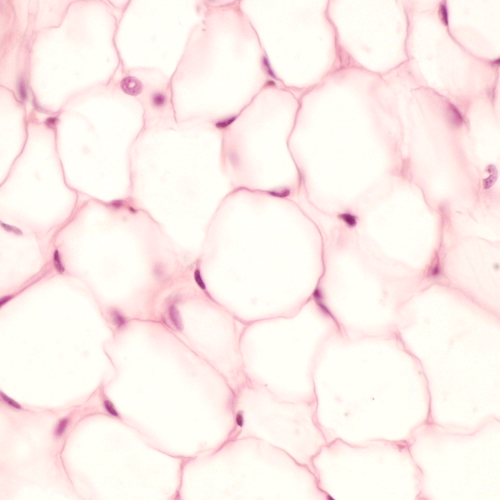

Mammals, including man, feed intermittently but consume energy continuously and use lipids as a temporary storage of energy rich material. Fat or adipose tissue is a type of connective tissue specialised for storage of lipids. There two distinct types of adipose tissue that differ in distribution, vascularity and metabolic function.